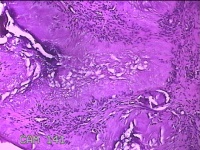

左外踝包块

性别

男

年龄

31岁

临床诊断

皮下结节

一般病史

发现左外踝包块1年余。

标本名称

大体所见

灰白暗红色包块1.8x1.3x0.7cm一个,表面糜烂,切开包块,内见大量石灰样物,内壁粗糙。

去了解病史,应该是痛风结节。